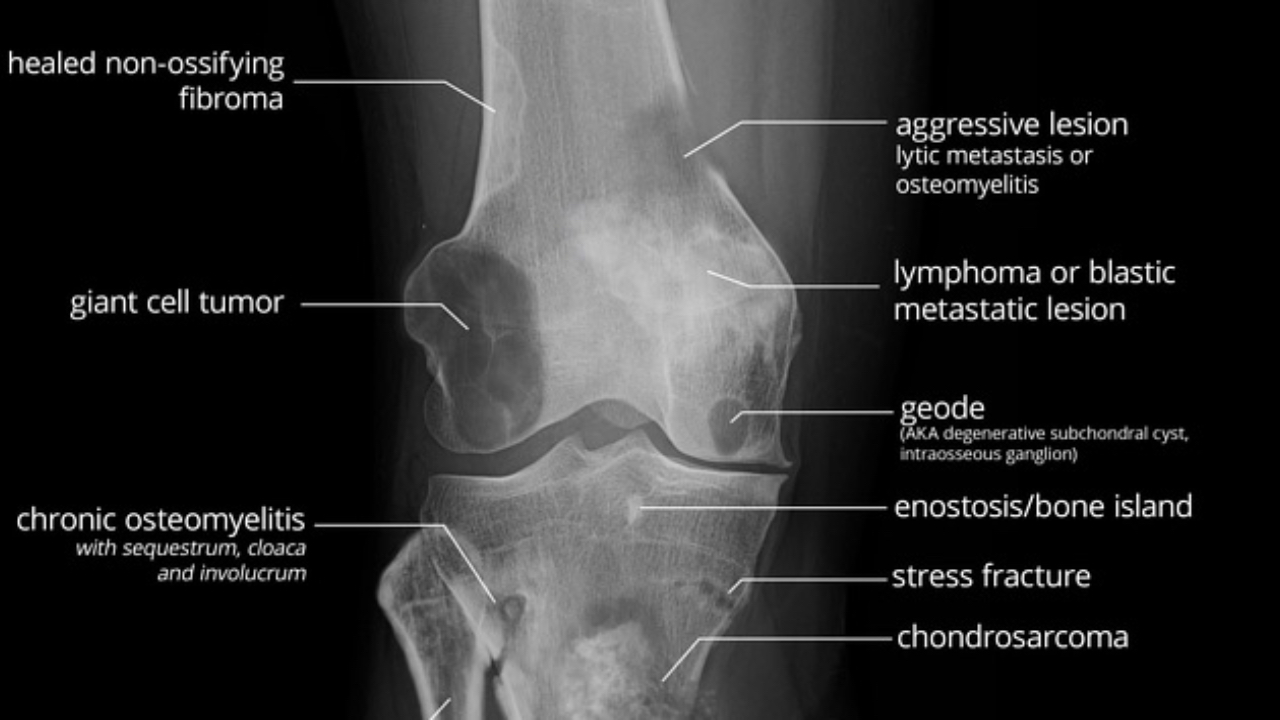

Tumors vs Tumor-Like Processes DXI on NBCE Part III: How to Stay Calm and Think Clinically

Tumors and tumor-like processes are one of the most anxiety-provoking categories in the Diagnostic Imaging Interpretation (DXI) portion of NBCE Part III.

Not because students can’t learn the material—but because they assume:

“If it’s a tumor question, I have to know the exact diagnosis.”

NBCE doe...